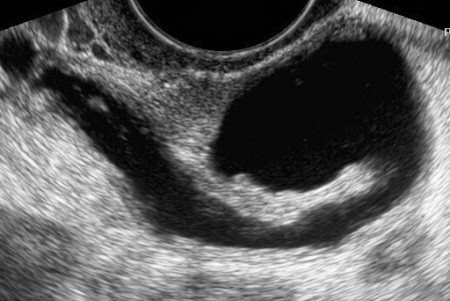

Все зависит от УЗИ аппарата. Где я ходила фибрии видно было, при гидросе там кишка и вы бы на экране ее увидели. Вот пример с инета, на хорошем узи сделан, трубу видно и сразу понятно, что есть что. Если у вас ни такой снимок, то диагноз еще рано ставить.